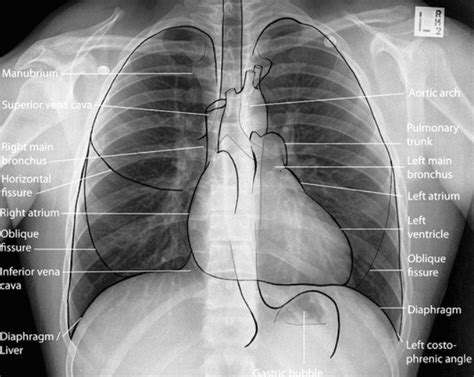

When an X-ray beam is directed at your body, different tissues absorb the radiation to varying degrees. Dense materials, like bone, which are packed tightly together, absorb more X-rays. Softer tissues, like muscles and organs, absorb fewer X-rays. The X-rays that aren’t absorbed pass through to a detector on the other side, usually a digital sensor or photographic film. This creates a radiograph , which is essentially a shadow picture. Bones appear white or light gray because they block the X-rays, while air-filled areas, like your lungs, appear black because the X-rays pass through them easily. Everything else falls somewhere in between, giving us a detailed, albeit grayscale, image of your internal structures. It’s this difference in absorption that allows doctors to see things like fractures, infections, or even foreign objects inside you without having to cut you open. Pretty neat, huh?